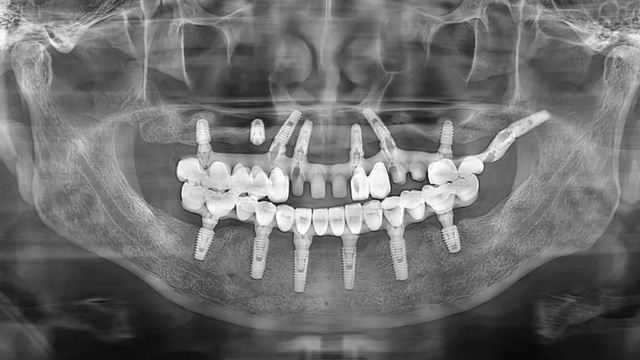

王先生的口腔全景片(2021年9月/新橋口腔成都玉雙院區(qū))